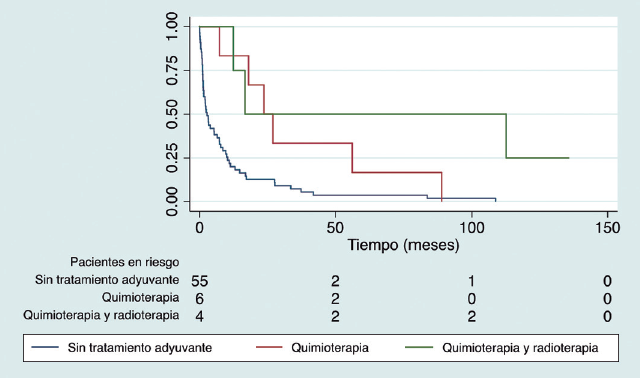

Julio César Núñez Villegas, Sergio Mauricio Rubel Cohen, Gabriel Alfredo Cavada Chacón, Laura Segovia González, Carlos Luis Matus Floody, Antonio Sa Cunha, Vilma Rodriguez, Rodrigo Abularach Cuellar

|

|

|